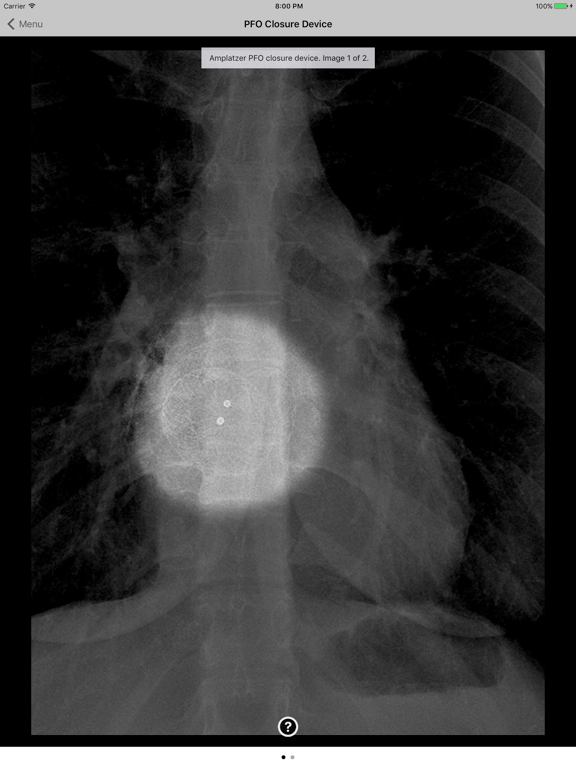

Introducing the Atlas of Medical Devices on Chest Radiography – one of the largest and most comprehensive collections of medical devices on chest radiography in existence. This app is an outstanding resource for physicians, physicians-in-training, and many healthcare providers who encounter medical devices on chest x-rays in daily practice. Review and explore the appearances of common and uncommon medical devices, organized by category. Search for a medical device in seconds using this app's lightning quick search feature.

· Countless images, organized into the following categories: Common Cardiac Conduction Devices, Less Common Cardiac Conduction Devices, Vascular Devices, Airway Devices, Enteric Devices, Neurological Devices, Musculoskeletal Devices, and Miscellanenous Devices.

· Tap the caption icon to read more about the device and to see it highlighted on the chest radiograph.